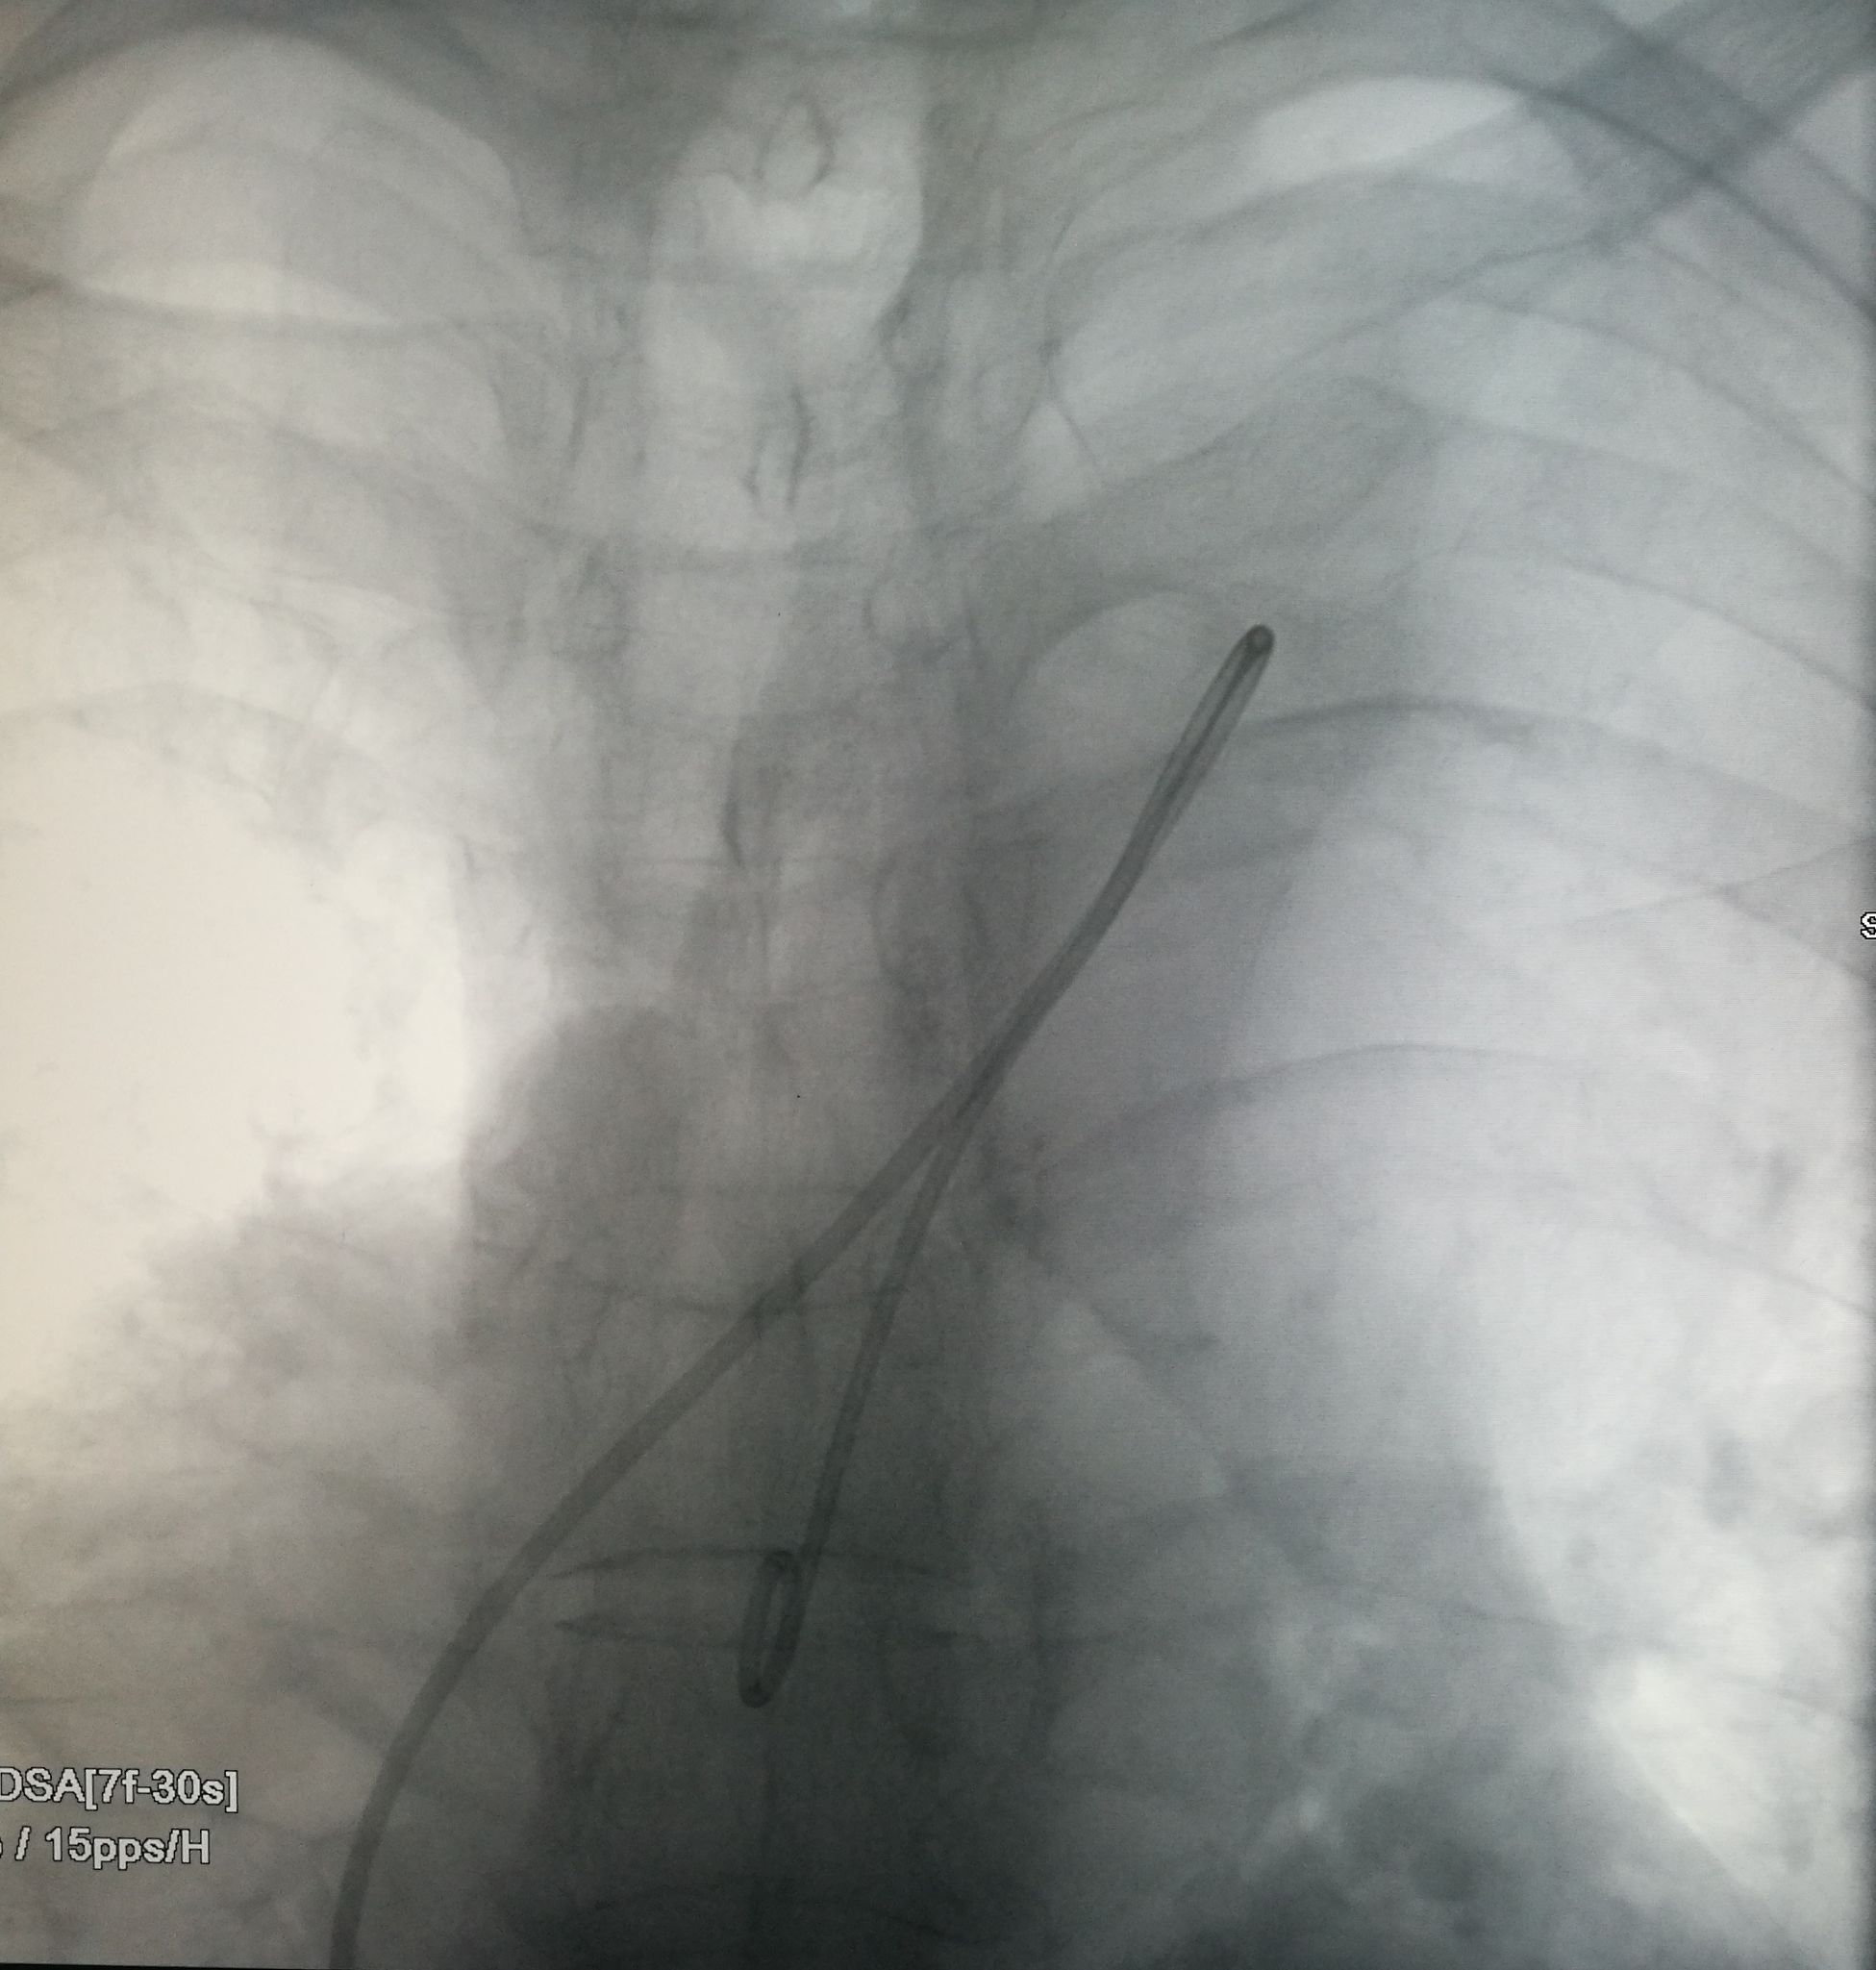

手术在局麻下进行,经右股动脉穿刺置管到升主,经左桡动脉穿刺植入金标猪尾导管,造影,为确认真假腔,加做右前斜位造影,确认股动脉导管在真腔内,测量后植入覆膜支架。由于扭曲严重(腹主,膈肌附近,弓降),支架最初并未贴服大湾侧,支架送过锁骨下动脉后适当回撤,请拉释放导丝,此时支架整体向大弯侧轻微移动,考虑应力已经得到缓解。完全释放支架,定位良好,封堵完全无内漏。